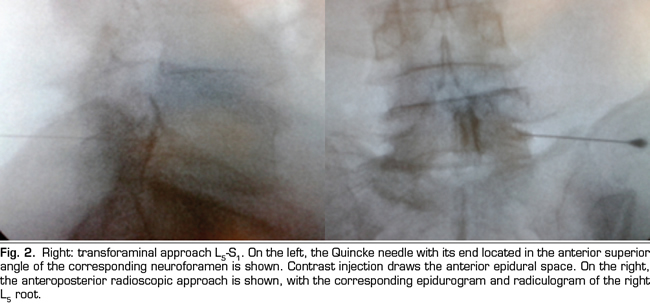

The procedure was performed in the surgical room. A peripheral venous catheter was placed with the patient on ventral decubitus position. Asepsis was conducted with alcoholic chlorhexidine and the local anesthesia was performed with 0.5 % lidocaine. Eighteen 3 1/2 or 4 3/4 inches tuohy needles (depending on patient size) were used for the parasagittal interlaminar technique. In the anteroposterior radioscopic view, the needle was inserted into the L4-5 or L5-S1 interlaminar spaces, using the tunnel vision technique, homolateral parasagittal of the side corresponding to the radicular pain (Figure 1). Loss of resistance was performed with saline. In the lateral view, a 4 mL contrast injection (Omnipaque©) was administered and the presence of anterior, posterior or both epidurograms was recorded (Figure 1). In the anteroposterior view the presence of radiculogram was recorded (Figure 1). A vial of betamethasone (12 mg of a mixture of phosphate and betamethasone acetate in 2 mL of solution) was then administered diluted with 3 mL of 0.5% lidocaine (total solution: 5 mL). The technical quality of the procedure was determined with the presence of paresthesia or concordant pain during the injection, and radiological data such as presence of radiculogram (Figure 1). Twenty two, 3 1/2 or 4 3/4 inches quincke needles were used in the transforaminal group and inserted using the oblique, lateral and anteroposterior radiological views.

The technical quality of the epidural steroid injection was evaluated in 21 out of 26 procedures performed with the parasagittal interlaminar approach. Anterior epidurograms, that is, achievement of the solution on the ventral epidural space, was obtained in 15 (71 %) of the patients (Figure 1 left); 17 (85 %) patients referred pain or paresthesia in the radicular territory during the injection, and a radiculogram was found in 12 (60 %) patients.